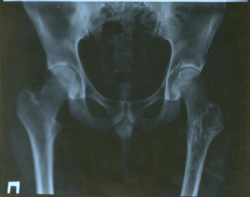

Прошу посмотреть снимки и высказать, есть ли в суставах проявления артроза и сужение суставной щели.

1) Врач местойк поликлинники считает что есть двухсторонний коксартроз

2) Другой врач поликлинники считает что суставы абсолютно здоровы

3) КДО при больнице считает что есть левый коксартроз.

1. Сколько лет больному? Артроз 1 стадии, неравномерное сужение суставной щели можно ставить любому взрослому человеку старше 30-40 лет, и никто его не опровергнет.

2. У данного пациента несомненное последствие дисплазии левого тазобедренного сустава, а именно ненормальная антеторсия левого бедра.

3. Настораживает структура большого вертела левой бежренной кости, но неясно, возможно это артефакты.

Ну, что с вами делать, что за дозированный подход к информации, все проверяете? Тогда, безусловно, левосторонний коксартроз (хотя и не диспластичный). Если нет совсем недавних снимков и есть клинические показания, можете поисключать возможность рецидива ОБК: КТ/МРТ.

Я не могу измерить, это всего лишь фото, а не натуральный снимок. Но визуально сужен наружный отдел щели левого сустава.